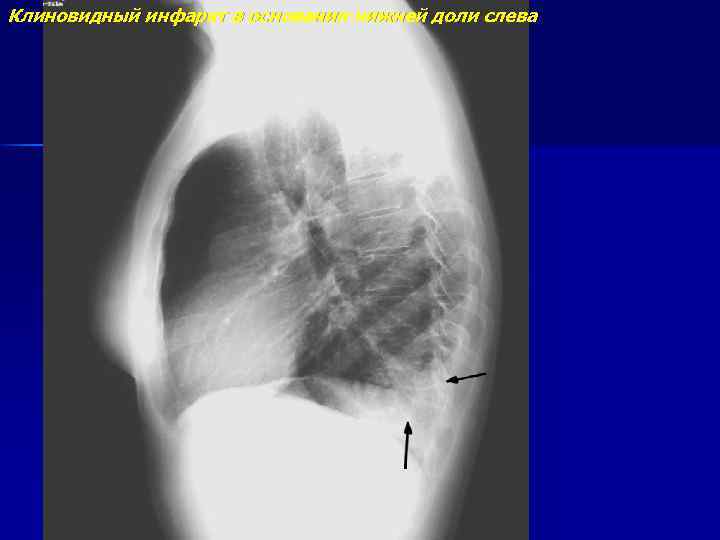

Клиновидный инфаркт в основании нижней доли слева

Клиновидный инфаркт в основании нижней доли слева (продолжение)